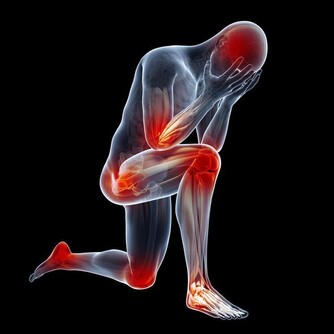

■腿部衰老的8大預警信號

1、腿腳沒有以前靈便了,稍多走點路,就會發酸發脹。

2、用點力或者站的時間稍長,就會腰酸腿疼。

3、步速越來越慢,偶爾走快點,會覺得腿腳不聽使喚。

4、 即使是夏天,也經常會感到小腿肚涼颼颼的,有時還會從臀部一直涼到腳後跟。

5、 抽筋次數增多。

6、雙腿腫脹。

7、 靜脈曲張,腿部血管非常清晰。

8、髖膝關節疼痛,甚至有摩擦磨損、卡住動不了的感覺。